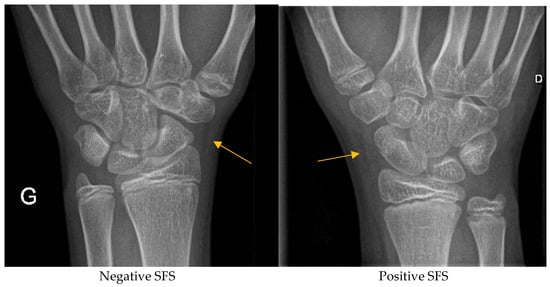

Scaphoid Fat Stripe Sign: Is It a Reliable Radiological Sign of Scaphoid Fracture in Children?

- Banerjee, B.; Nashi, M. Abnormal scaphoid fat pad: Is it a reliable sign of fracture scaphoid. Injury 1999, 30, 191–194. [Google Scholar] [CrossRef] [PubMed]

- Carver, R.A.; Barrington, N.A. Soft-tissue changes accompanying recent scaphoid injuries. Clin. Radiol. 1985, 36, 423–425. [Google Scholar] [CrossRef]

- Corfitsen, M.; Christensen, S.E.; Cetti, R. The anatomical fat pad and the radiological “scaphoid fat stripe”. J. Hand Surg. Br. 1989, 14, 326–328. [Google Scholar] [CrossRef] [PubMed]

- Terry, D.W., Jr.; Ramin, J.E. The navicular fat stripe: A useful roentgen feature for evaluating wrist trauma. Am. J. Roentgenol. Radium Ther. Nucl. Med. 1975, 124, 25–28. [Google Scholar] [CrossRef] [PubMed]